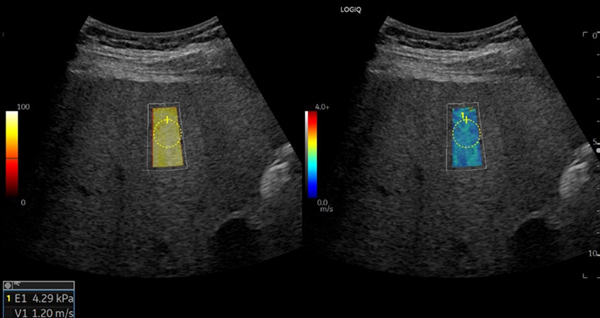

特長<4>

Shear Wave Elastography(SWE)*

組織の硬さをワンクリックで視覚化。Quality Mapにより,信頼性を色と数値で評価し検者間誤差を低減し安定したデータ取得をアシスト。